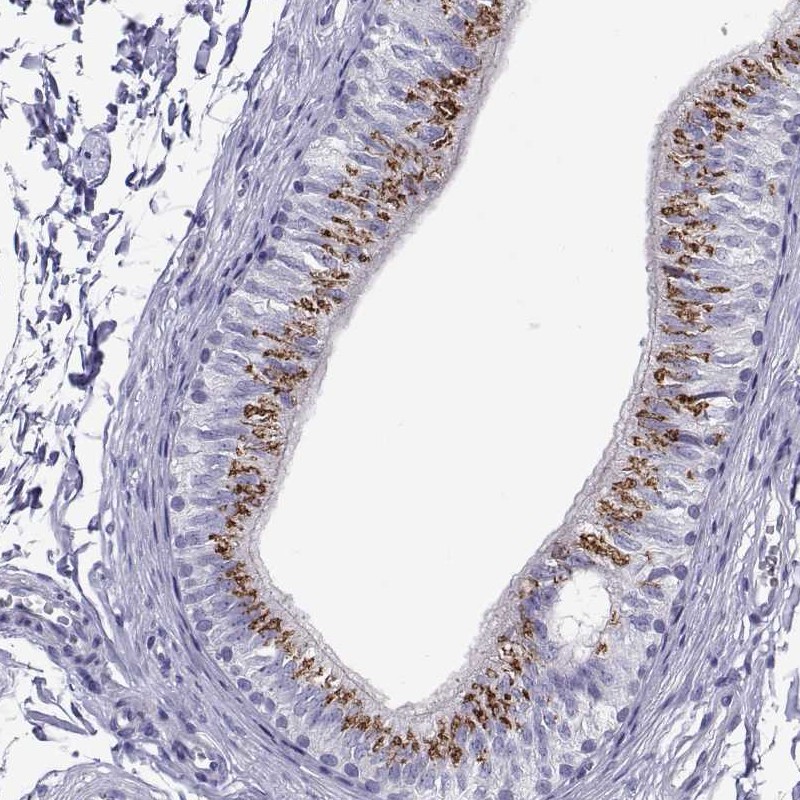

Immunohistochemistry analysis in human epididymis and fallopian tube tissues using Anti-RNASE12 antibody. Corresponding RNASE12 RNA-seq data are presented for the same tissues.